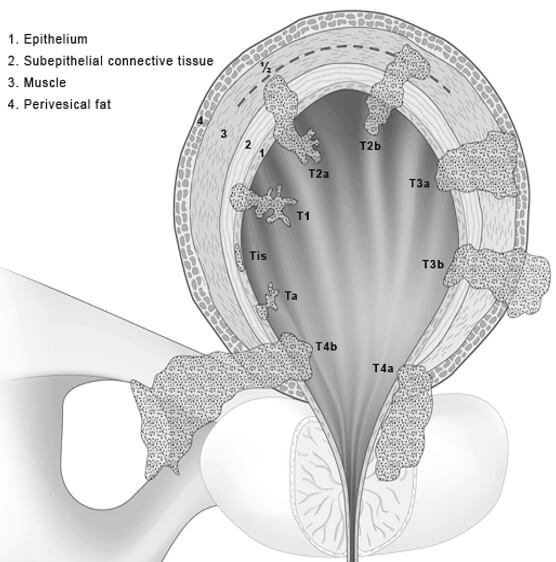

Illustration of different pathological stages of bladder cancer. Stage …

Classification Of Bladder Tumors : TNM stage classification of bladder …

Stages of bladder cancer from Meyer et al., (2002). Bladder cancer can …

Overview of staging and grading of bladder cancer tumor. The figure was …

Classification Of Bladder Tumors : TNM stage classification of bladder …